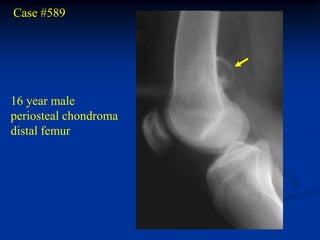

Case #589

16 year male

periosteal chondroma

distal femur

AP view